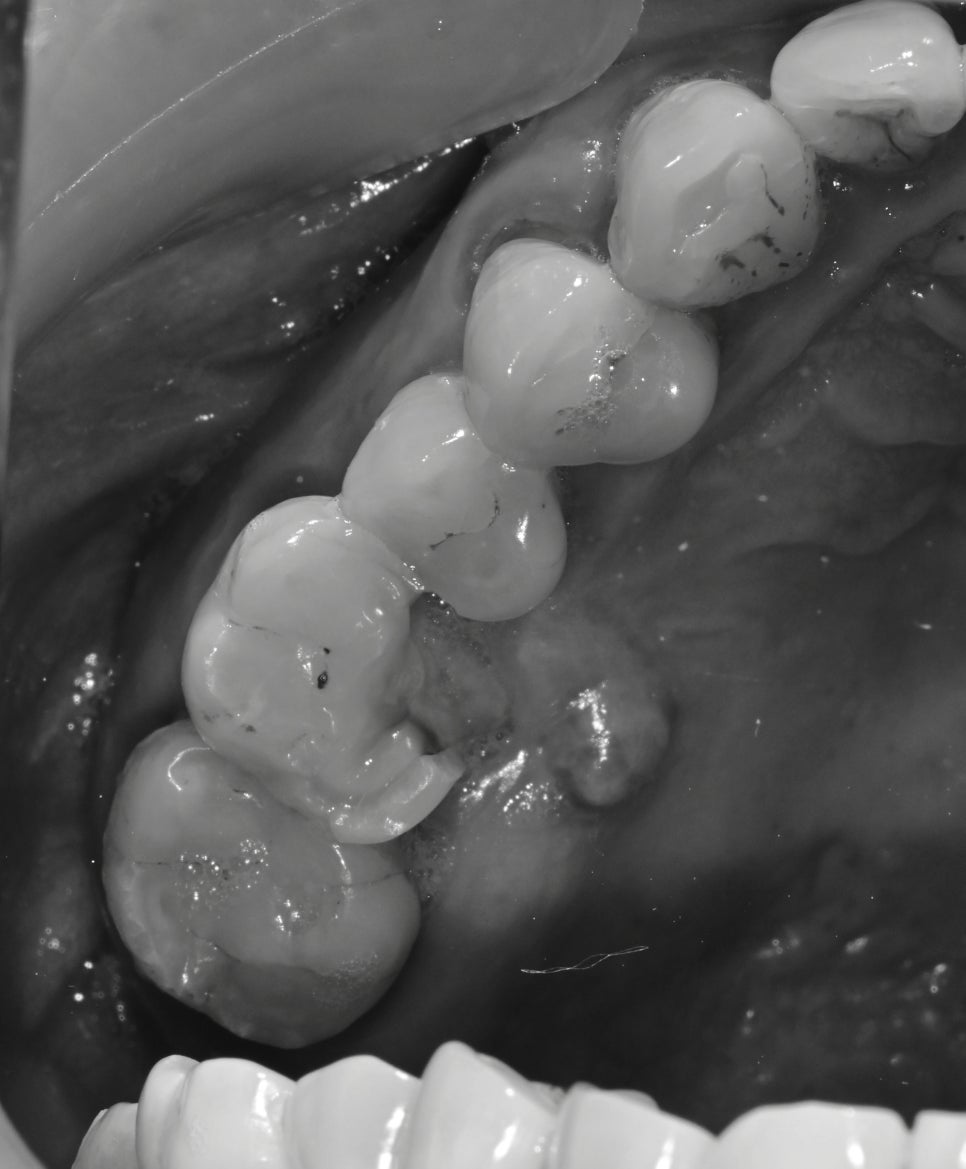

처음 환자분을 검진하기 전 사진을 봤을 때

왼쪽 치아가 다수 상실된 상태에서 우측으로 주로 씹다 보니 가장 일을 많이 하는 치아인

첫 번째 큰 어금니가 망가진 것이 보였습니다.

구내 사진을 찍고 검진을 했을 때 이 치아는 예후가 좋지 않다고 설명을 드렸습니다.

그리고, 이미 치아의 마모도 및 치아의 깨진 흔적을 봤을 때 굉장히 강한 저작력과 그로 인해

치아에 금이 가있을 확률이 높았습니다.

잇몸뼈 또한 입천장 쪽으로 녹아 있었기 때문에 이 치아는 그동안 너무 많은 일을 해왔고, 수명이 얼마 남지 않았습니다.